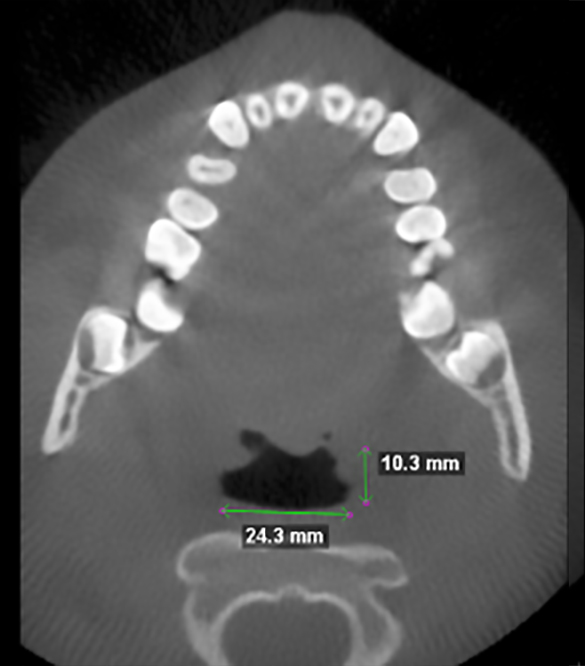

The patient below experiences the following symptoms:

- Struggling to breathe during sleep

- Snoring

- Waking unrefreshed

- Daytime fatigue

- Easily distracted

- Neck pain

- Buzzing in both ears once or twice a week for about a one minute duration.

Before and after images of patient after 9 months of successful treatment: